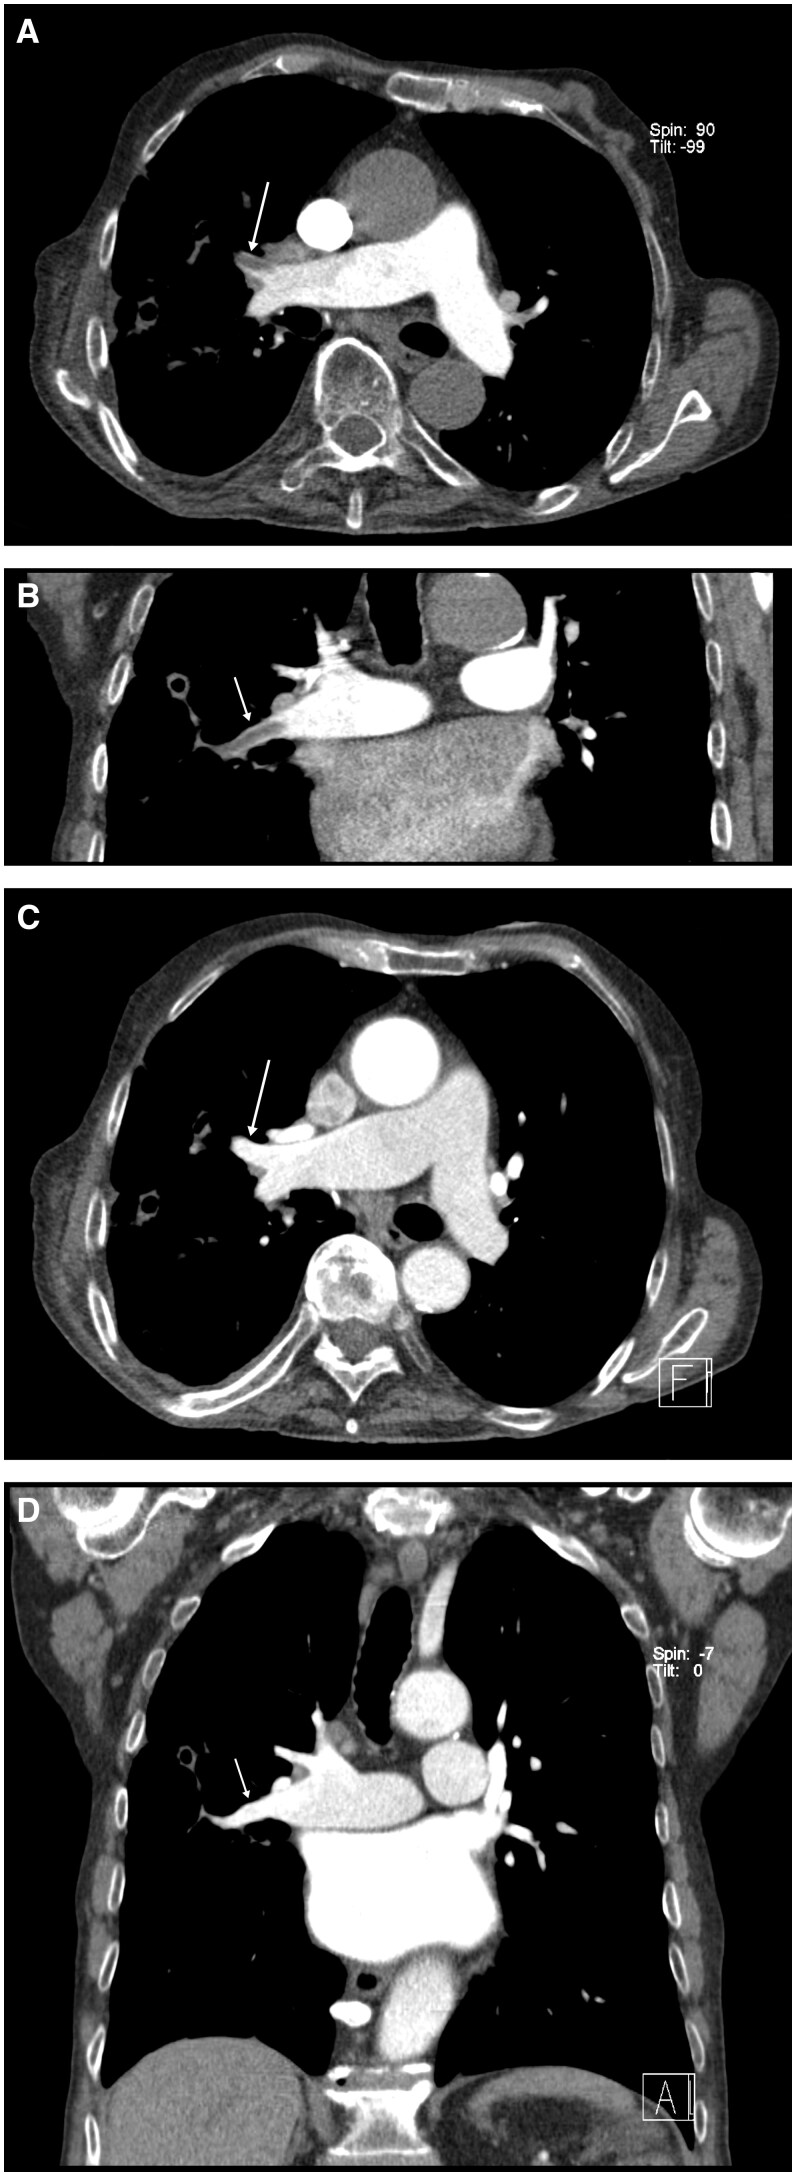

We present the case of an 81-year-old patient, who was transferred to our department for diagnostic work-up and treatment of hemoptysis of the right lung. Two-phase contrast-enhanced chest CT revealed filling defects in right upper lobe and middle lobe pulmonary artery during the pulmonary-artery phase who vanished in the subsequent aortographic phase, consistent with systemic-artery-to-pulmonary-artery fistulas (SA-PAFs) of right bronchial artery mimicking pulmonary embolism. Selective bronchial catheter-arteriography confirmed bronchial SA-PAFs and bronchial artery embolization was performed effectively and without complication. For the best of our knowledge, this is the first case of a bronchial systemic-artery-to-pulmonary-artery-fistula mimicking PE directly correlated and proved with bronchial artery angiography.